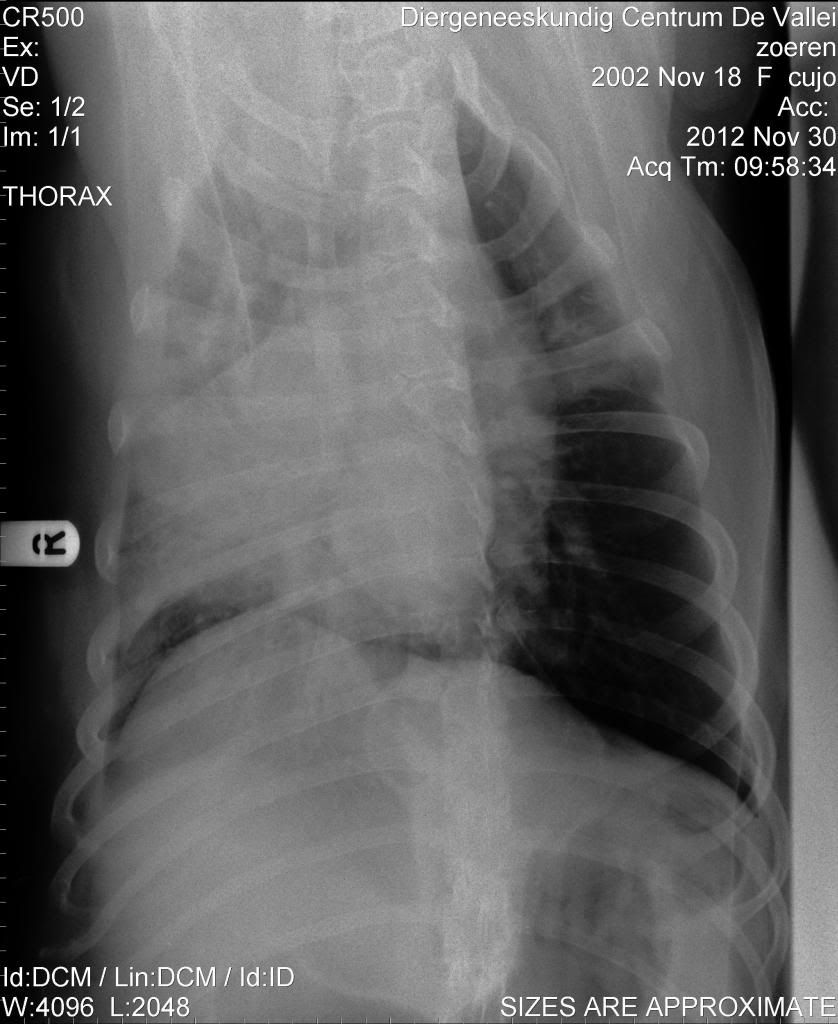

Ben benieuwd wat jullie denken te zien

Dat is ook wat ik er in zie, meer kan ik er niet van maken.Jeannettebo schreef:Rechterlong ziet er niet lekker uit...en wellicht een wat groot hart?

Denk dat jij in de goede richting zit. Moet er wel bij zeggen dat ze kennelhoest heeft en dan de zware vorm en tegen een longontsteking aan zit.Jeannettebo schreef:Rechterlong ziet er niet lekker uit...en wellicht een wat groot hart?

Ik denk dat de longontsteking er al zit, rechts meer dan links, links begint in een bovenkwabDemi schreef:Denk dat jij in de goede richting zit. Moet er wel bij zeggen dat ze kennelhoest heeft en dan de zware vorm en tegen een longontsteking aan zit.Jeannettebo schreef:Rechterlong ziet er niet lekker uit...en wellicht een wat groot hart?

Over welke foto heb je het dan? De dierenarts waar ik net was deed erg moeilijk en gaf ons het gevoel ga maar lekker naar huis met je oude hond. Toen ik vroeg of ze geen ab moest hebben voor de longontsteking was het antwoord nee en ik kreeg dexametason en plaspillen meeJeannettebo schreef:Ik denk dat de longontsteking er al zit, rechts meer dan links, links begint in een bovenkwabDemi schreef:Denk dat jij in de goede richting zit. Moet er wel bij zeggen dat ze kennelhoest heeft en dan de zware vorm en tegen een longontsteking aan zit.Jeannettebo schreef:Rechterlong ziet er niet lekker uit...en wellicht een wat groot hart?

TARAKfreskin schreef:Ik heb totaal geen verstand van rontgenfoto's, maar dit ziet er niet goed uit, volgens mij. De rechterlong lijkt bijna helemaal geen lucht meer te bevatten, maar een ruimte innemend proces of ontsteking/verbindweefseling. Het hart lijkt me inderdaad ook vergroot. Maar dit is voor mij echt gissen..... Ik zou inderdaad zo snel mogelijk een longspecialist inschakelen.